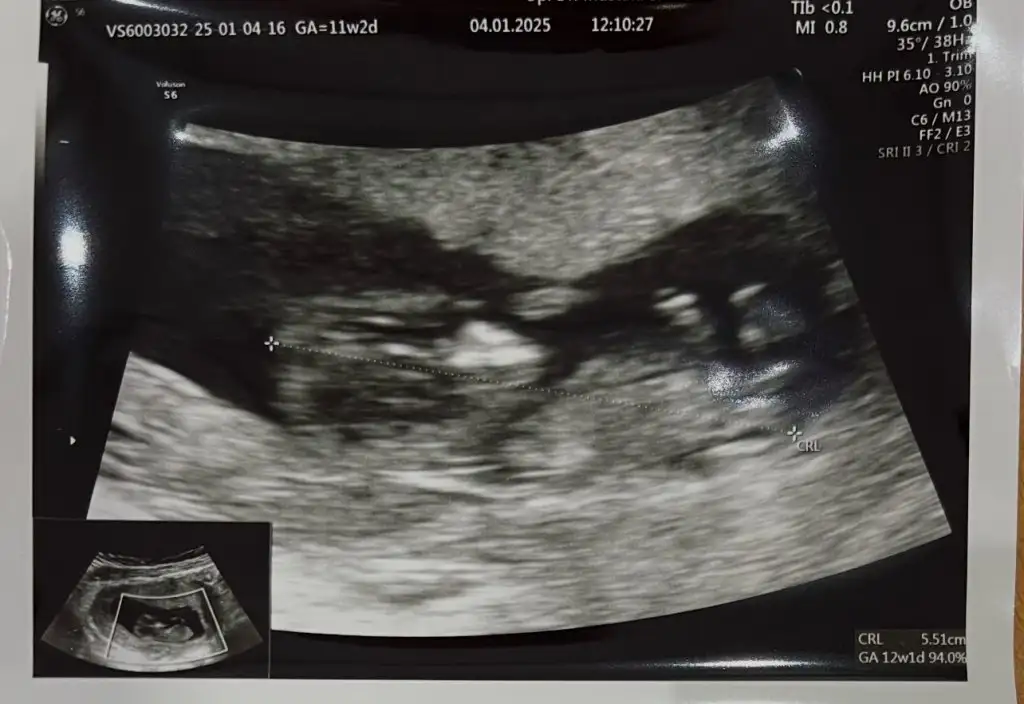

Merhaba 11+2 haftalık ultrason cinsiyet tahmini yapabilir misiniz acaba ?

Buda 12+2 haftalık hala aynı fikirde misiniz?Kıza benzettim ben

Buda 12+2 haftalık hala aynı fikirde misiniz acaba ?Annesi maşallah tosununayanlış görmüyorsam oğlumdaki aynı çıkıntı burada da, sağlıcakla gelsin inşallaaaah,

Evet hala erkeğe benzettimBuda 12+2 haftalık hala aynı fikirde misiniz?